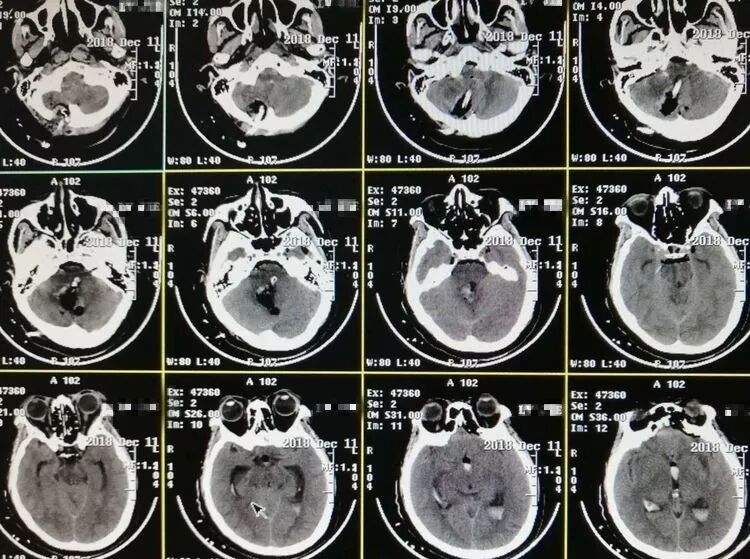

突发头痛,意识不清1小时。既往高血压病史多年,未系统治疗。自主呼吸深大,瞳孔正常大小。CT显示小脑蚓深部大量脑内血肿,IV脑室受压移位,III脑室及侧脑室内积血,左侧丘脑少量出血。

术后病人意识水平明显改善,刺激睁眼,双侧肢体自主活动。复查头CT显示小脑血肿清除满意,左侧丘脑内血肿未见增加,治疗中…

手术行枕下正中入路,应用锁孔通道技术,吸除脑内血肿,进一步清理IV脑室内积血,责任血管止血可靠,术毕。